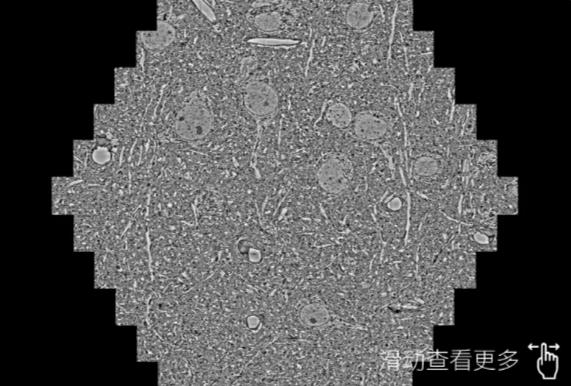

鼠脑切片。左图使用南阳蔡司南阳扫描电镜MultiSEM706对165μmx143pm面积区域成像,耗时仅需1.5秒。右图为鼠脑切片中30μm区域放大效果。样品由芝加哥大学B.Kasthuri提供。

使用蔡司高速南阳扫描电镜MultiSEM对1mm²人脑皮层组织进行高分辨成像,并对其中的各种细胞结构进行三维重构分析。左图展示了2x3mm²组织平面中锥体神经元的三维重构效果。右图显示了局部体积神经元三维重构。图像由哈佛大学chtman实验室提供,渲染图由D. Berger 制作。